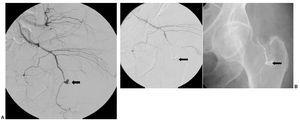

Once lesiones fueron roturas arteriales con formación de pseudoaneurisma de una arteria musculoesquelética (fig. 1) y 9 fueron lesiones en una arteria visceral (fig. 2), 4 de las cuales fueron lesiones de la arteria gastroduodenal (fig. 3), tres secundarias a complicaciones de una duodenopancreatectomía cefálica y otra a una punción directa con un catéter de drenaje 10 french de un absceso secundario a una colecistectomía.

Fig. 2. (A) (caso 7). Arteriografía selectiva de arteria hepática en la que se aprecia la fístula arterio portal (flecha a la derecha), el tracto hepático de la biopsia (flecha hacia abajo) y en fase tardía el relleno de un radical biliar (flecha hacia arriba). (B) Arteriografía hepática en la que se objetiva el molde sustraído de Onyx y el cierre de la fístula con ausencia de llenado del árbol portal y biliar (flecha).